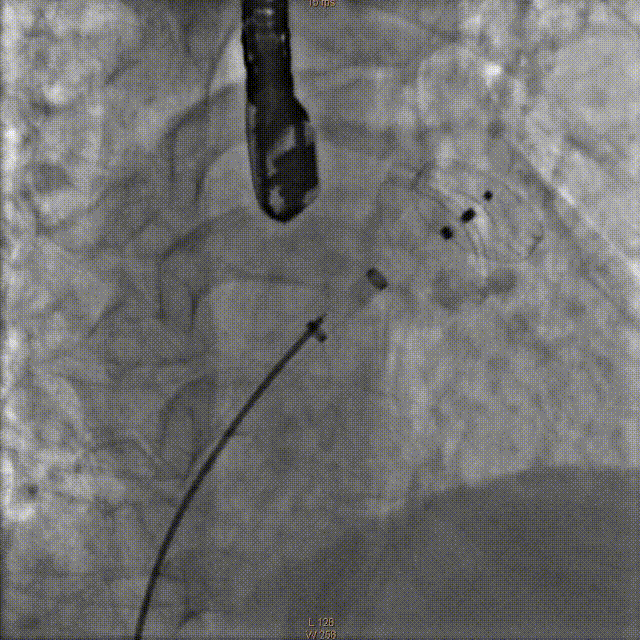

覆盖盘释放并造影

牵拉实验固定稳妥,无明显心包积液,透视下释放左心耳封堵器于左心耳。退出输送鞘管至右房测右房压12/5mmHg:撤出传送钢丝及血管穿刺鞘。